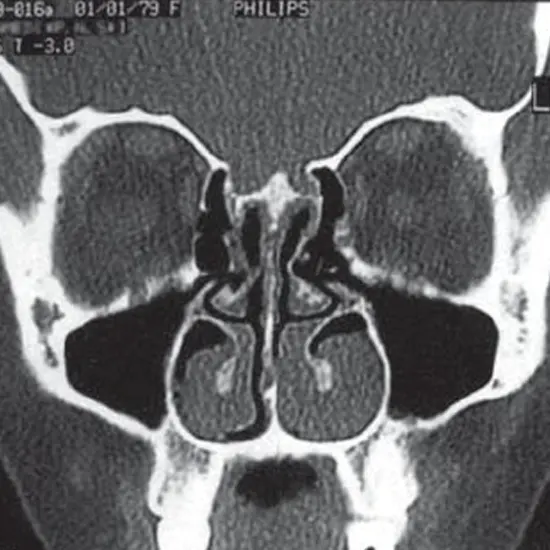

HRCT PNS CORONAL acronyms for high resolution computed tomography paranasal sinuses – coronal. It is an imaging scan that uses a small amount of radiation to view the details of the sinus and evaluate the paranasal sinus cavities. Paranasal sinus cavities are a group of 4 hollow air-filled spaces within the face bone surrounded by nasal cavities. The doctor recommends the scan to confirm the existence of tumor, Its size and its location.

HRCT (High-Resolution Computed tomography) screening of the HRCT PNS coronal is a non-invasive radiology test used to evaluate the condition of the paranasal sinus cavities and surrounding tissue. HRCT PNS Coronal is done to look for the conditions of the paranasal sinus cavities and the surrounding area.